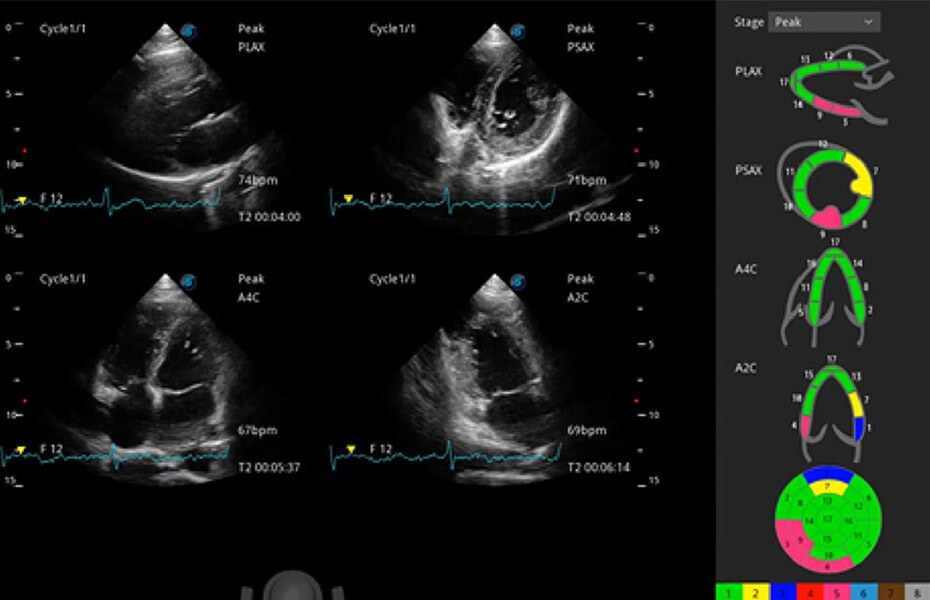

ProPet 60 作为一款高端台式动物超声设备,为动物医生的日常诊断提供了一系列贴合动物临床需求、解决临床实际问题的高级成像功能。凭借全系列高清探头,满足医生对腹部、心脏、生殖、浅表、肌骨等成像的所有需求,切实帮助您提升检查效率,提高诊断信心。

兽用彩色多普勒超声诊断系统